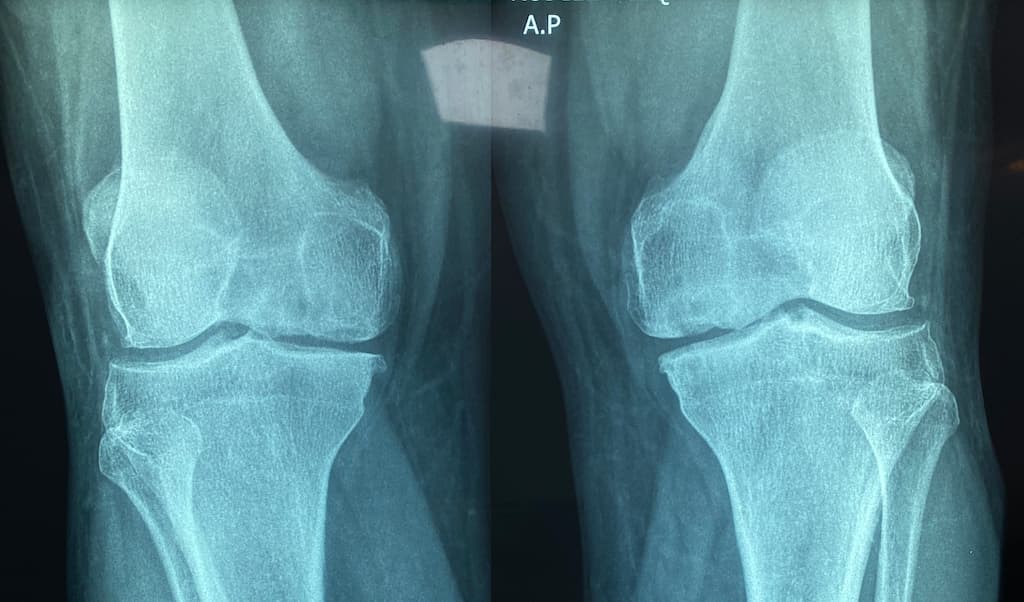

If chronic knee pain is interfering with your life in Cypress, TX, knee replacement surgery performed by Dr. Catherine Cahill, M.D., could be the solution. This procedure replaces worn or damaged knee joints with durable implants designed to restore mobility and relieve pain. Dr. Cahill offers both partial and total knee replacement options, ensuring Cypress patients receive the most appropriate treatment for their condition. From enjoying outdoor activities at Telge Park to running errands with ease, knee replacement surgery can help you move without discomfort.

Knee replacement surgery is a highly effective solution for Cypress, TX, residents struggling with chronic knee pain due to severe osteoarthritis or other degenerative joint conditions. Dr. Cahill provides both partial and total knee replacement options, helping patients regain function and enjoy a more active lifestyle.

Depending on the severity and location of knee arthritis, Cypress patients may benefit from partial knee replacement procedures that focus on specific areas of the joint, such as the medial, lateral, or patellofemoral compartments. Dr. Cahill’s expertise ensures that each patient receives the most appropriate treatment for their unique needs.